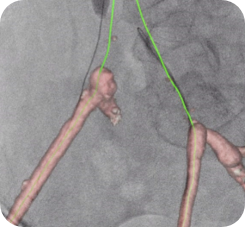

Planifier